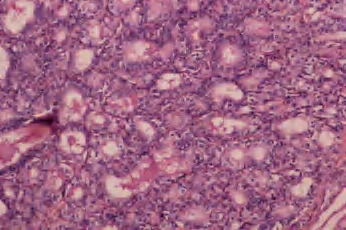

(1)嗜酸细胞腺瘤 单发,界限清楚,包膜完整,具有特征性的红褐色外观,常见中央区瘢痕形成。构成肿瘤的细胞有富含颗粒的嗜酸性胞浆,核大和明显的核仁,胶质常浓染并可形成类似沙砾体的结构,局部可见到乳头结构(图3-32至图3-34)。

图3-33 嗜酸性细胞腺瘤